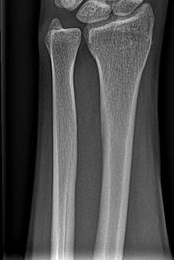

ПЕРЕЛОМ ЯКОЇ КІСТКИ І ЯКОЇ ЇЇ ЧАСТИНИ ВИ БАЧИТЕ НА РИСУНКУ?

варіанти відповідей

ДИСТАЛЬНОГО ДІАФІЗА

HUMERUS

ULNA

RADIUS

ПРОКСИМАЛЬНОГО ЕПІФІЗА

ДИСТАЛЬНОГО ЕПІФІЗА

ДІАФІЗА

МЕТАФІЗА

РОЗПІЗНАЙТЕ КІСТКУ. ПЕРЕЛОМ ЯКОЇ ЇЇ ЧАСТИНИ ВИ БАЧИТЕ НА РЕНТГЕНОГРАМІ?

FEMUR, ШИЙКА

ЛІКТЬОВОГО ВІДРОСТКА

ПРОМЕНЕВОГО ВІДРОСТКА